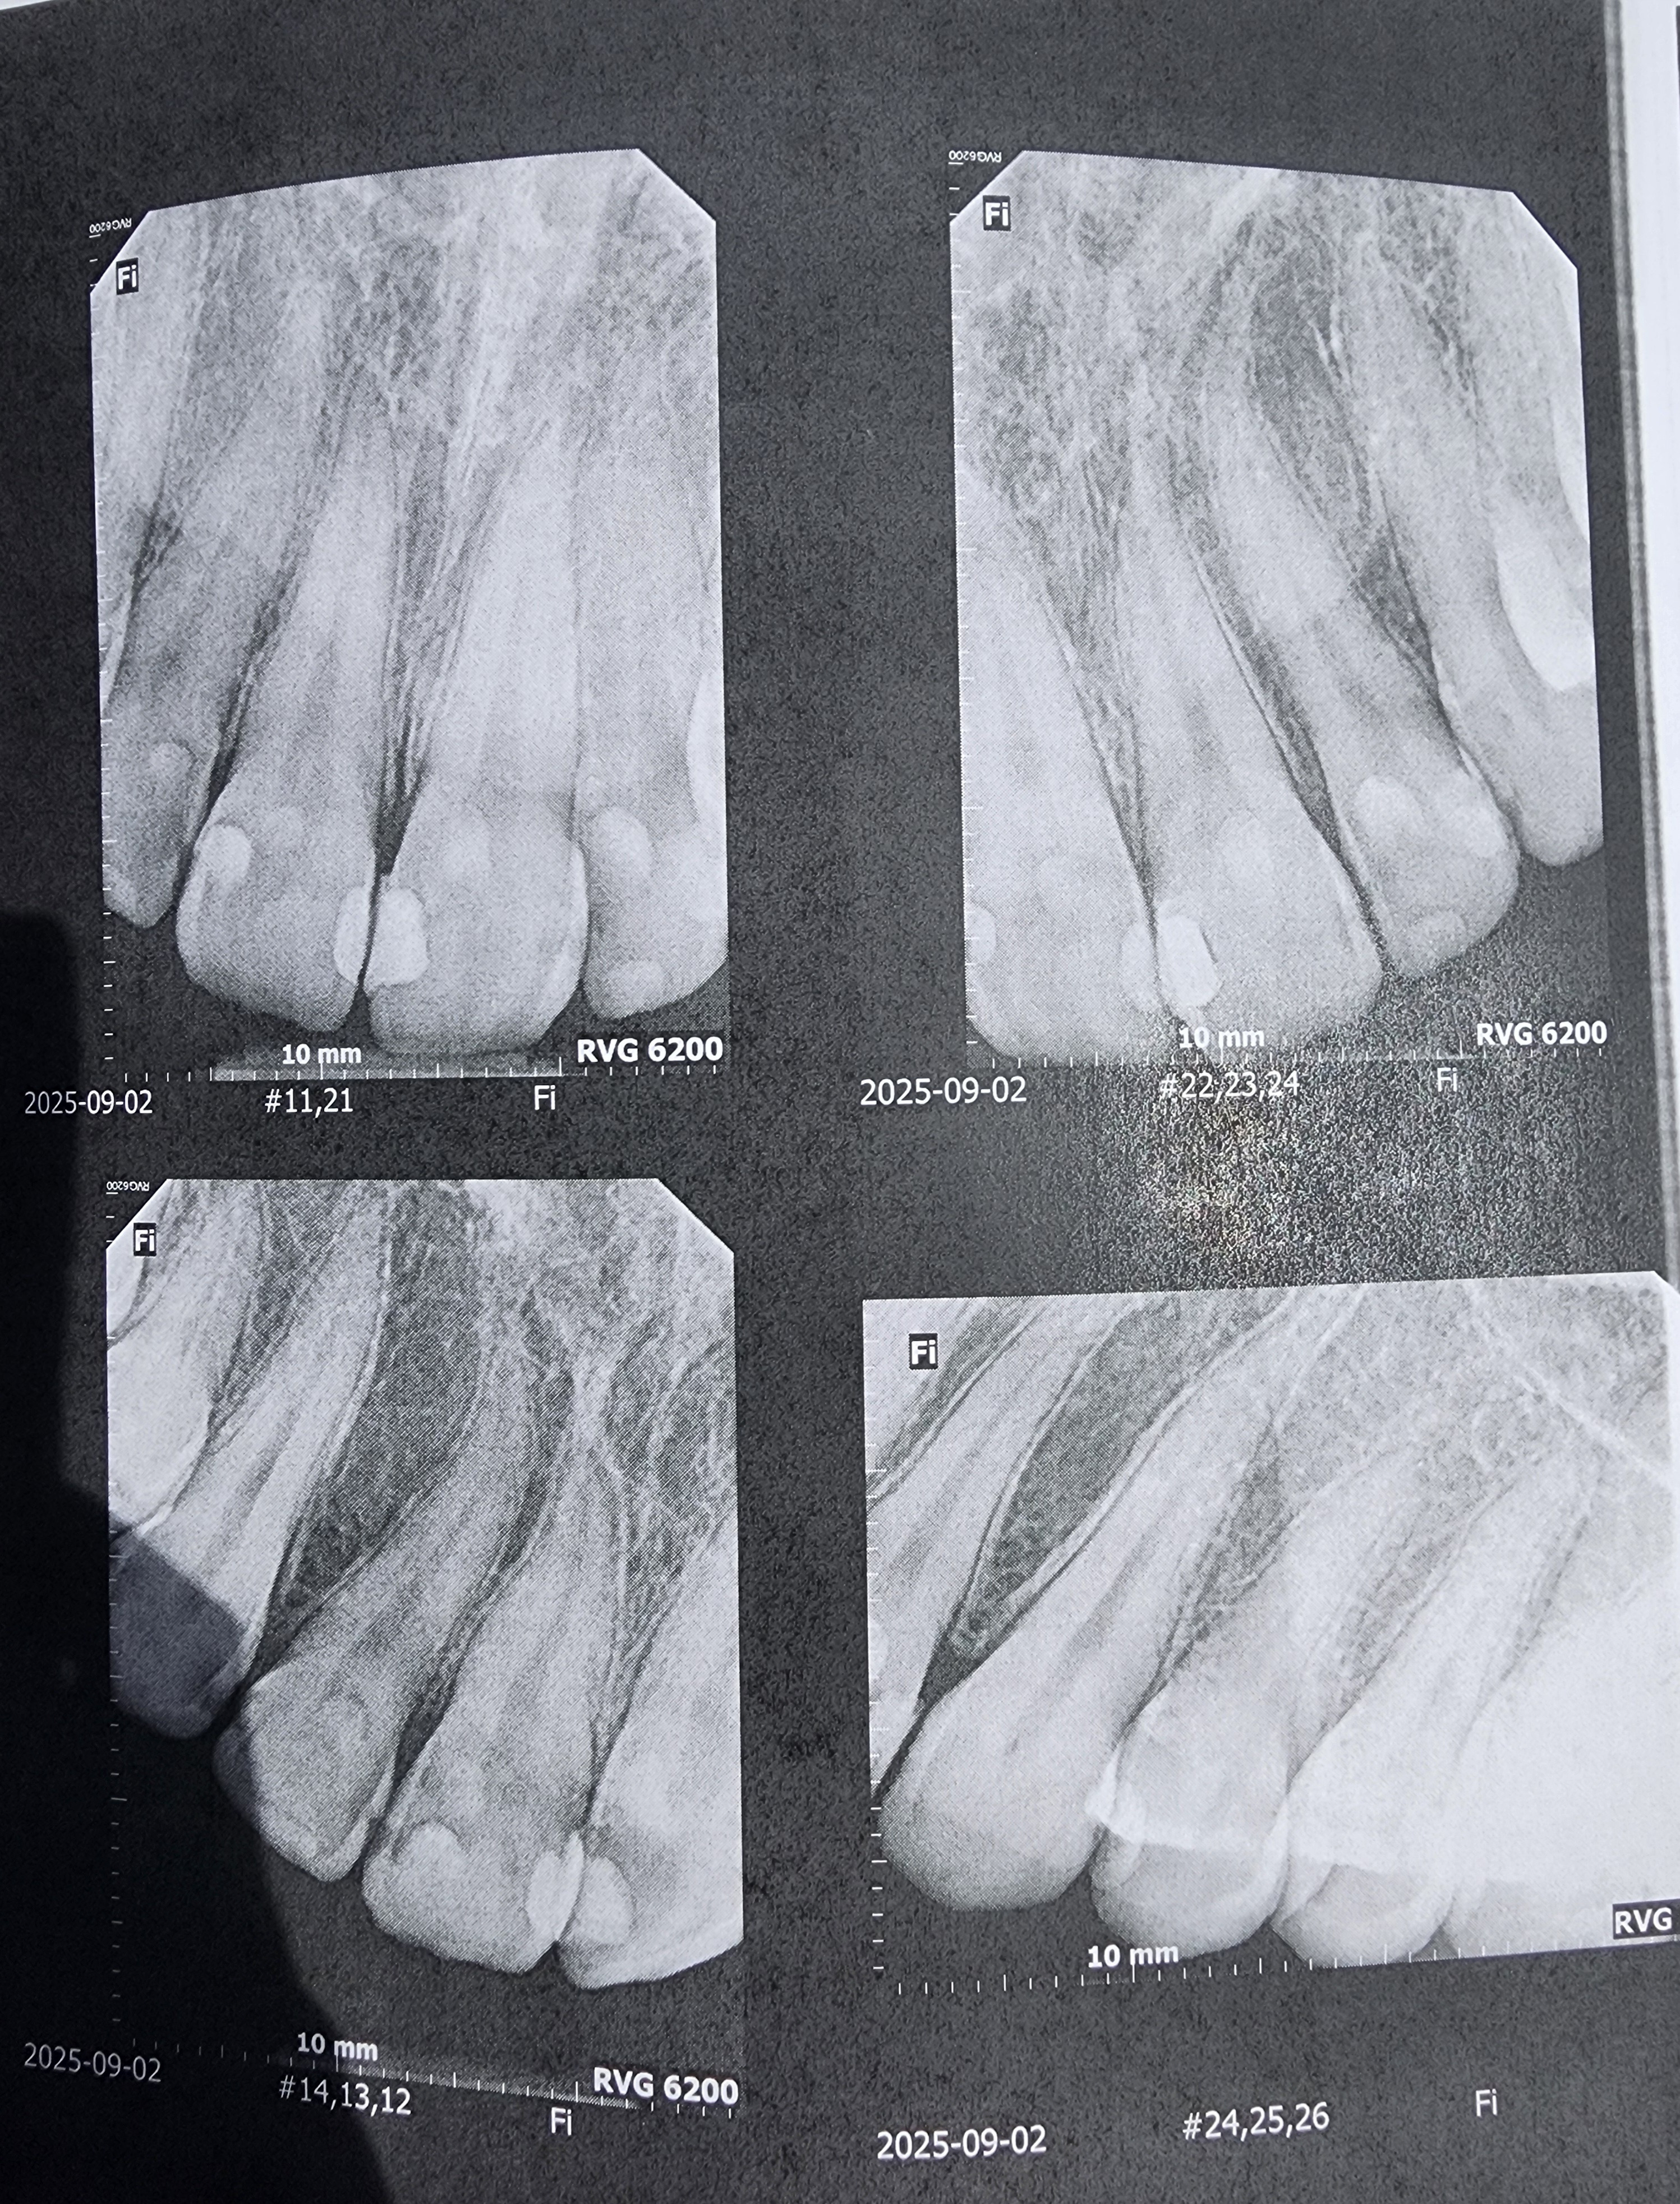

Hello. My name is Ash and those x-rays are of my not so good teeth. I knew that they weren't that good but they were worse than I could ever have imagined.

Due to an old dentist seemingly giving me bad fillings before leaving the practice, it seems I need 4 Crowns, 1 or 2 Root Canals, and a whole ton of fillings. I was prepared for a couple thousand but it seems they want about 12,400 in total. And this includes a dental plan card they let me sign up for to half the entire bill. They want me to pay before each appointment and at this point I dont know what I can do.

I am making this gofundme to at least get 12,000. this will cover the worst tooth that needs both the crown and root canal, the crowns, and all of the cavities. I have family willing to lend me the other 500 or so to get the cleaning done.